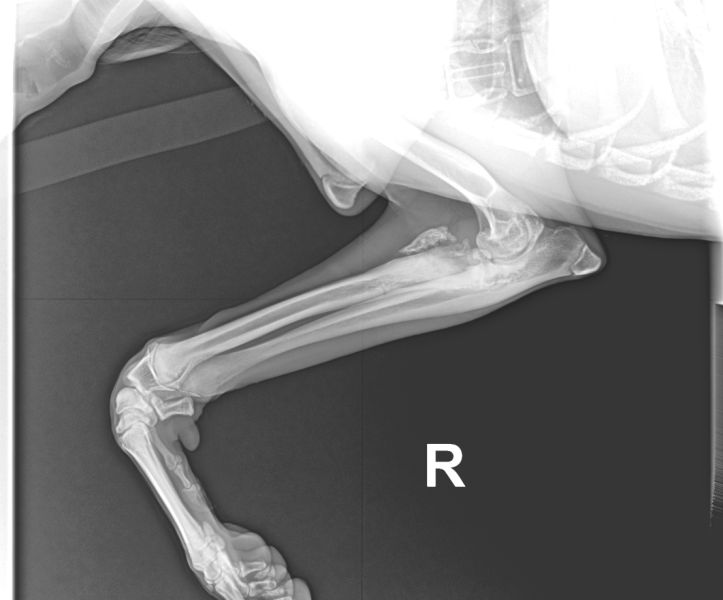

Nachdem sich nun fast 7 Monate gar Niemand für unseren Huckelberry interessierte, obwohl ihn sein angeknackstes Ellbogengelenk so gut wie gar nicht belastet, haben wir uns entschlossen, Huckelberry auf die "Paten -gesucht -Seite" zu verschieben.

Eine körperliche Behinderung reicht wahrlich aus, wir wollen seinem aufkeimenden Selbstbwußtsein nicht auch noch einen Schlag versetzen.